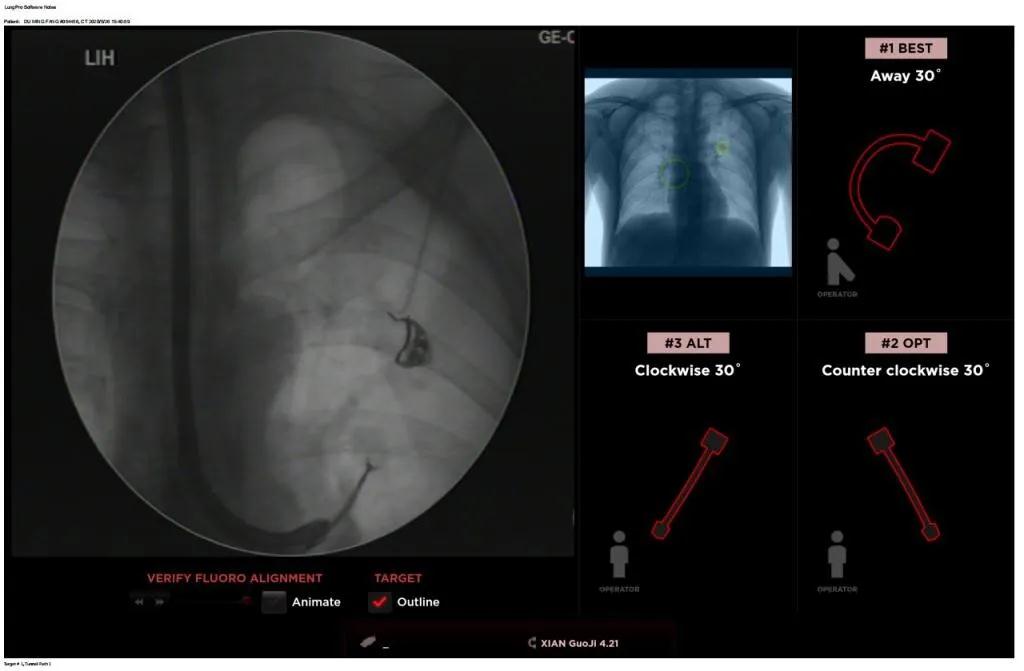

西安國際醫學中心醫院呼吸內科完成西北地區首例LungPro全肺導航系統引導下BTPNA手術

近日,西安國際醫學中心醫院胸科醫院歐陽海峰副院長完成西北地區首例LungPro全肺導航系統引導下經支氣管鏡跨肺實質肺外周結節活檢術。

患者是一位59歲的男性,入院診斷左固有上葉前段肺小結節,大小1.5cm*1.5cm。因為病灶與支氣管不相通,無法開展經支氣管自然腔道的活檢,而且病變距離胸壁較遠、肋骨阻隔進針線路、病灶周圍有血管包繞,如果進行CT引導下經皮肺穿刺活檢,則存在較大的氣胸、出血等并發癥的風險。

經過充分的討論后,歐陽海峰副院長決定為患者實施LungPro全肺導航系統引導的經支氣管跨肺實質肺外周結節活檢術。Broncus導航系統LungPro具有全球領先獨創的BTPNA技術(支氣管鏡下跨結節抵達術),可以實現對氣道外周孤立性肺小結節的精準定位,建立直接通往氣道外病變部位的通道,以實現全肺的診斷及后續治療。這項技術不僅彌補了現有支氣管鏡技術由于受限于病變部位是否有氣道可通向以及無法準確定位病變部位而造成的較低診斷率,同時還彌補了CT引導下經胸穿刺(TTNA)無法適用于某些特定部位如中央及肩胛骨等結節的問題,并且還避免了經胸穿刺給患者帶來氣胸、出血的高風險,可有效提高肺部結節及早期肺癌診斷陽性率,亦可用于早期肺癌的射頻消融或微波治療,具有微創、安全、同期雙肺診療等優勢。

BTPNA技術整合了虛擬導航支氣管鏡VBN、氣道內超聲rEBUS、TBNA、高壓球囊擴張、X線輔助等多項三、四級呼吸內鏡技術。歐陽海峰副院長有3000 TBNA、1000 rEBUS、500 VBN、800 球囊擴張方面的技術積累,10年來個人每年完成三、四級呼吸內鏡手術1200余例,這有效保障了BTPNA技術的順利開展。

團隊術前進行了精心的準備,通過高分辨率CT建立了導航路徑,在麻醉科手術室的配合下,借助LungPro引導順利的確定了病灶部位、建立隧道并實施活檢,術后患者恢復順利出院。